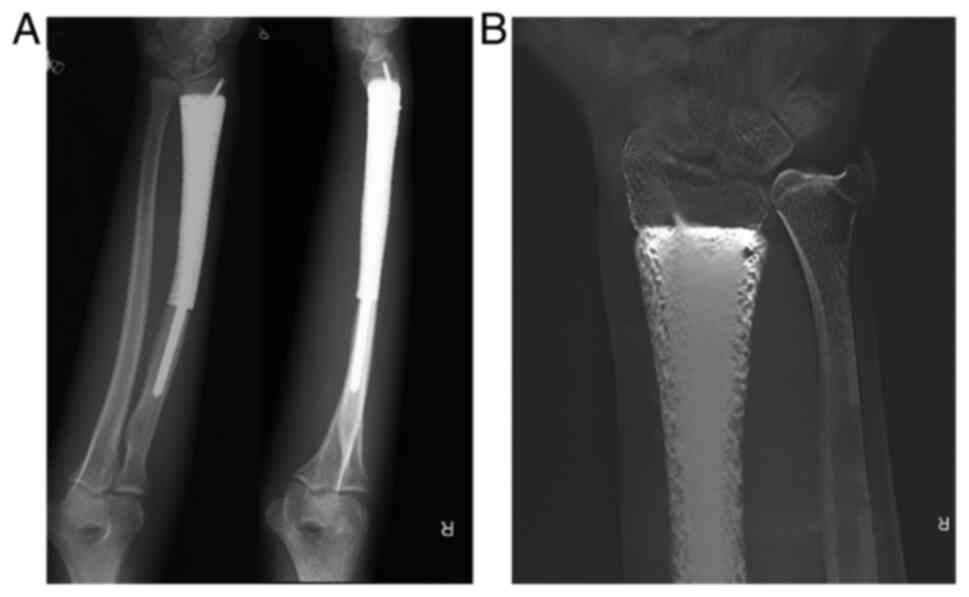

The patient underwent plain radiography and digital tomosynthesis (Shimadzu metal artifact reduction technology) of the right forearm postoperatively (Fig. 4A and B). During the first two weeks postoperatively, the affected limb was immobilized in a volar resting brace. The grip exercise was carried out from the first day postoperatively and, at 2 weeks after the surgery, dorsiflexion and palmar flexion were encouraged without weight-bearing of the affected limb while immobilizing the wrist. At 4 weeks postoperatively, the brace was removed and the patient was allowed to rotate the forearm. The patient then gradually increased the intensity of training and initiate weight-bearing on the affected upper limb according to the patient's tolerance and recovery progress. The patient was followed up monthly in the first 3 months, then trimonthly thereafter. Functional outcome was assessed by range of motion (ROM), the 1993 version of the Musculoskeletal Tumor Society (MSTS-93) score (12) (range 0 to 30; a higher score is desirable), the disabilities of the arm, shoulder and hand (DASH) questionnaire (13) (range 0 to 100; a lower score is desirable) and Mayo wrist score (14) (range 0 to 100; a higher score is desirable). Osseointegration was evaluated by digital tomosynthesis.

Figure 4

Postoperative imaging. (A) 24 month postsurgical anteroposterior and lateral radiographs. (B) Digital tomosynthesis showed the 3D prosthesis tightly integrated with the distal radius and partial bone substance could be observed to grow into the pores of the prosthesis.